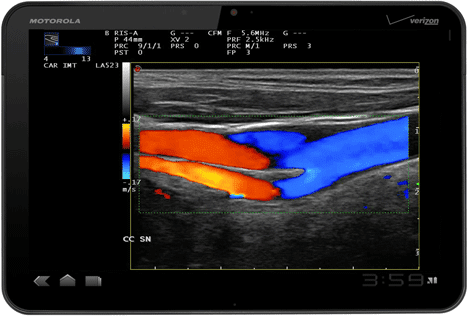

Μια ιταλική διαγνωστική εταιρία, η Esaote δείχνει πως μια σειρά συσκευών που χρησιμοποιούν υπερήχους, η σειρά MyLab line μπορεί να ‘μοιράζεται’ με ένα Motorola Xoom tablet τις εικόνες του, επιτρέποντας σε γιατρούς να ελέγχουν τις εξετάσεις και με συναδέρφους τους μακριά από τον ασθενή. Το πιο πιθανό δε είναι πως η λύση της εταιρίας δεν είναι μόνο για το Xoom αλλά αποτελεί σε κάθε περίπτωση μια ‘απάντηση’ σε λύσεις που έχουν ετοιμαστεί για ιατρικό προσωπικό με το iPad.

Η δυνατότητα να σταλεί η εξέταση υπερήχων σε ένα ελαφρύ και ισχυρό tablet με ισχυρό επεξεργαστή και HD οθόνη όπως το Motorola Xoom, επιτρέπει να υπάρχει πρόσβαση σε κλινικές πληροφορίες παντού και είμαστε σίγουροι πως θα δούμε πολλές τέτοιες λύσεις.